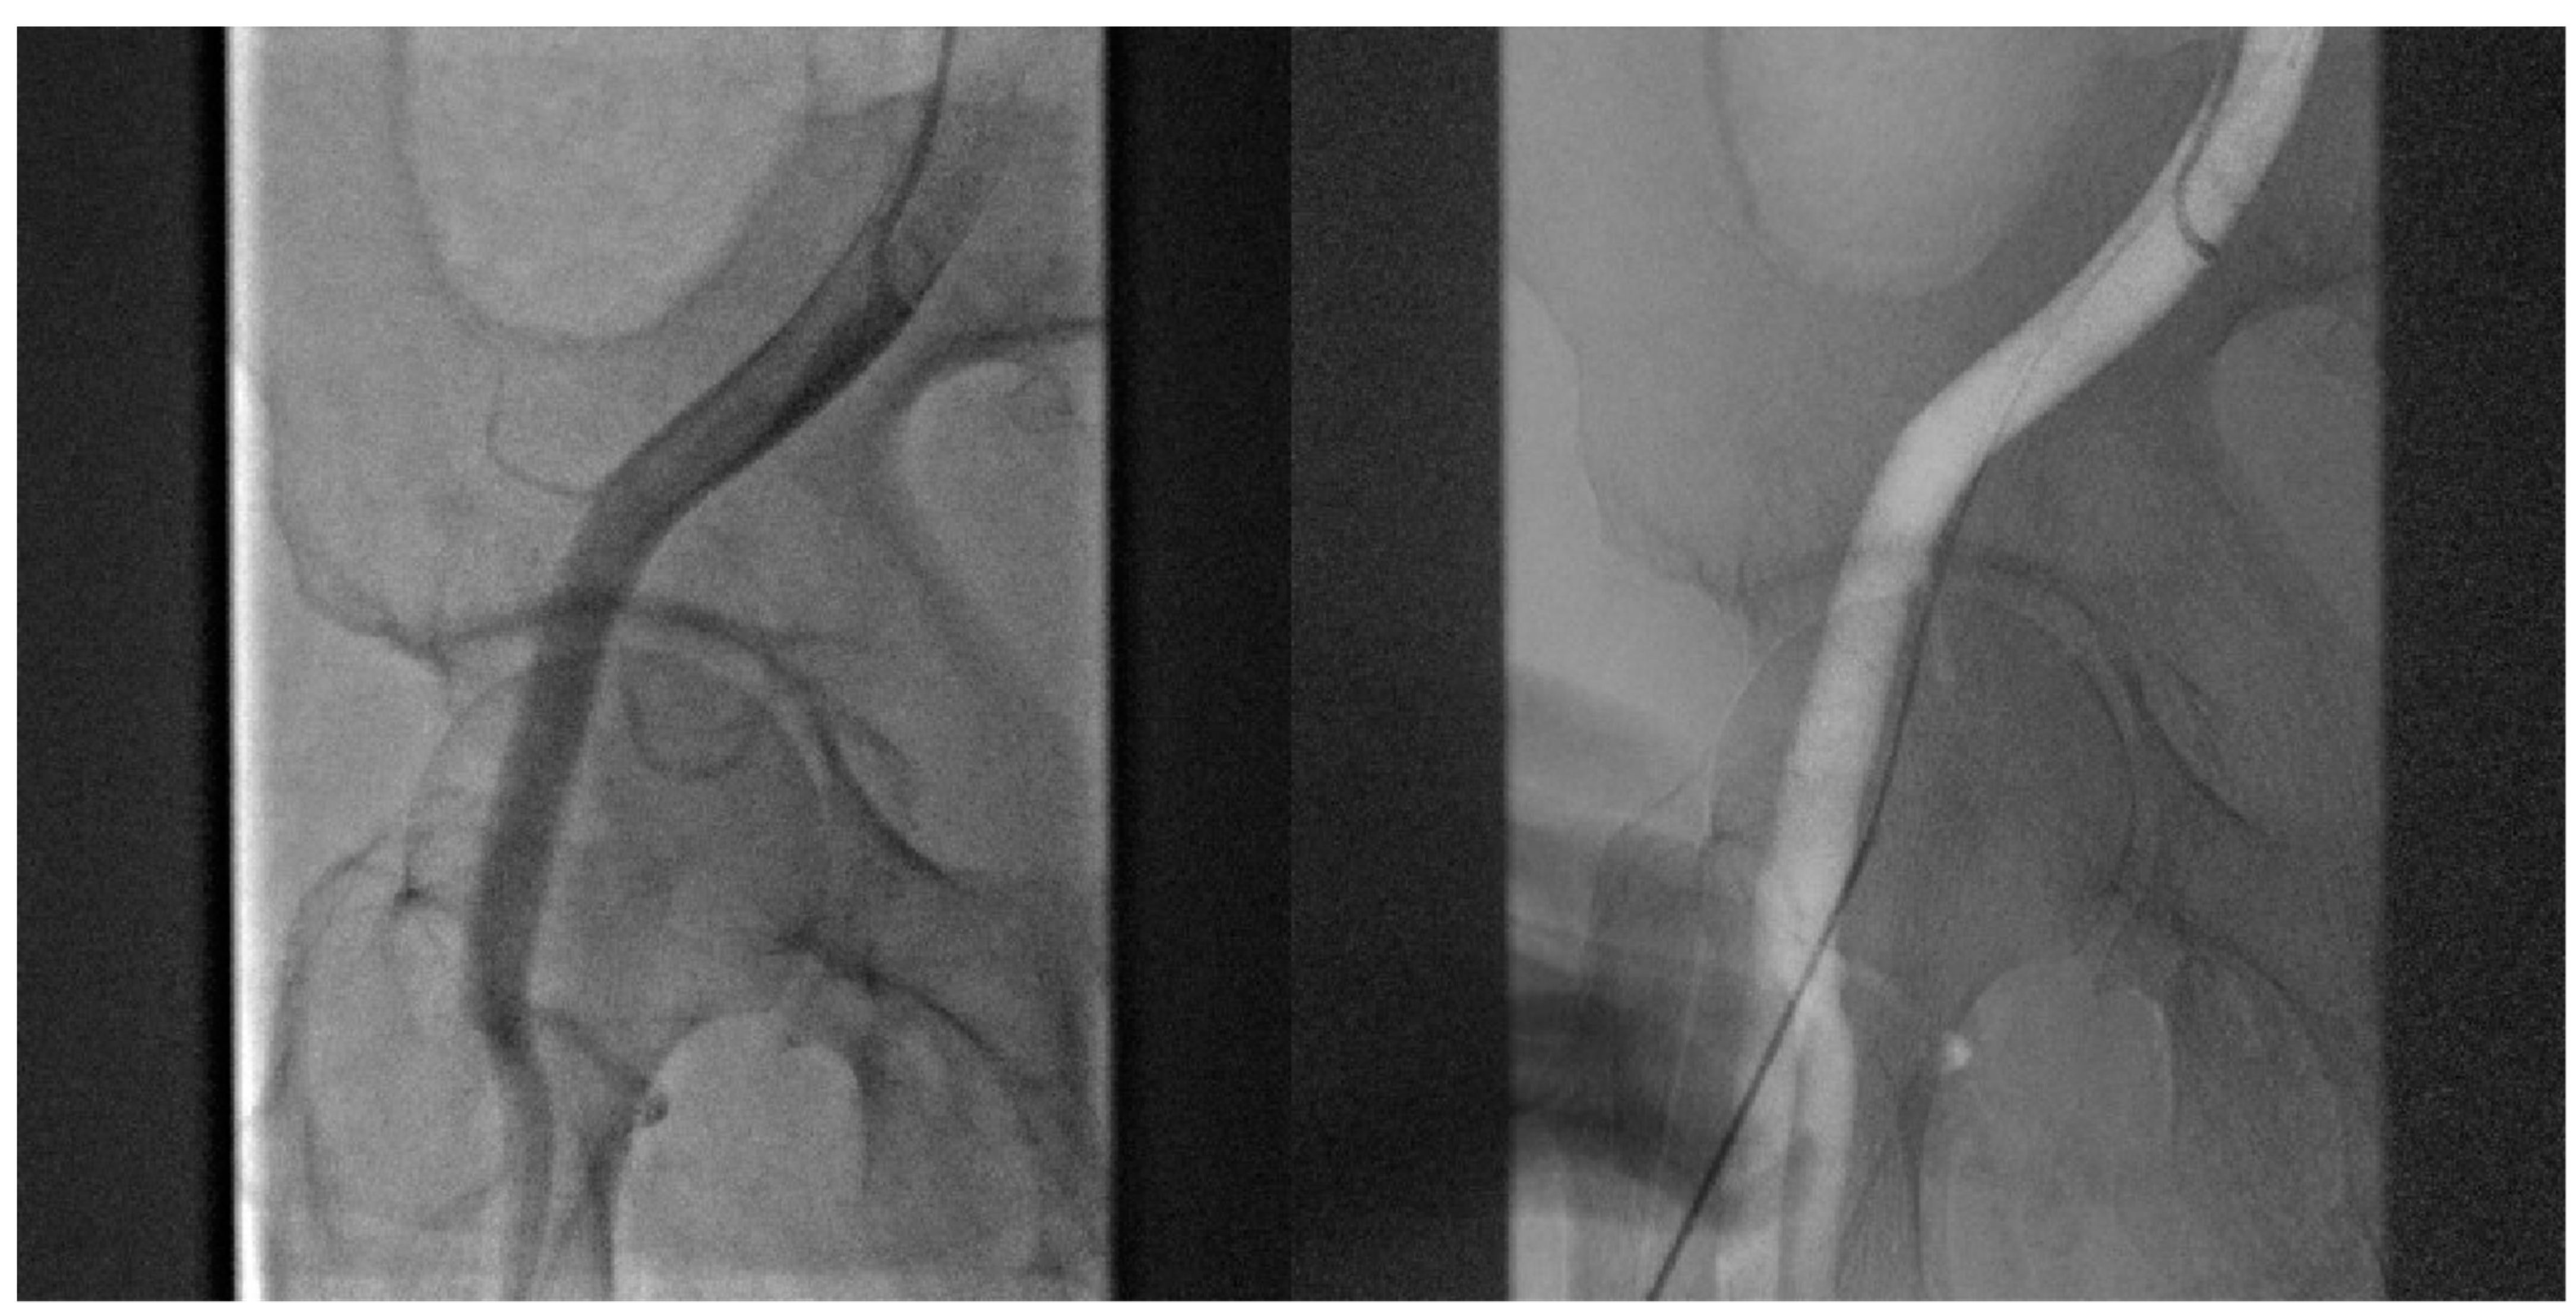

- Angiography-guided femoral puncture: A secondary access is necessary (radial or femoral) for the possibility of reaching the proximal part of the CFA to perform digital subtraction angiography (DSA) and road mapping Figure 3 to guide the puncture.

Figure 3. DSA allow to puncture in the correct site of CFA avoiding bifurcation and other small vessels.

- Cardiogenic shock pre-PPCI: Time is muscle. After basal coronary angiography, in order to place a pMCS the use of DSA would probably be the faster option Figure 8.